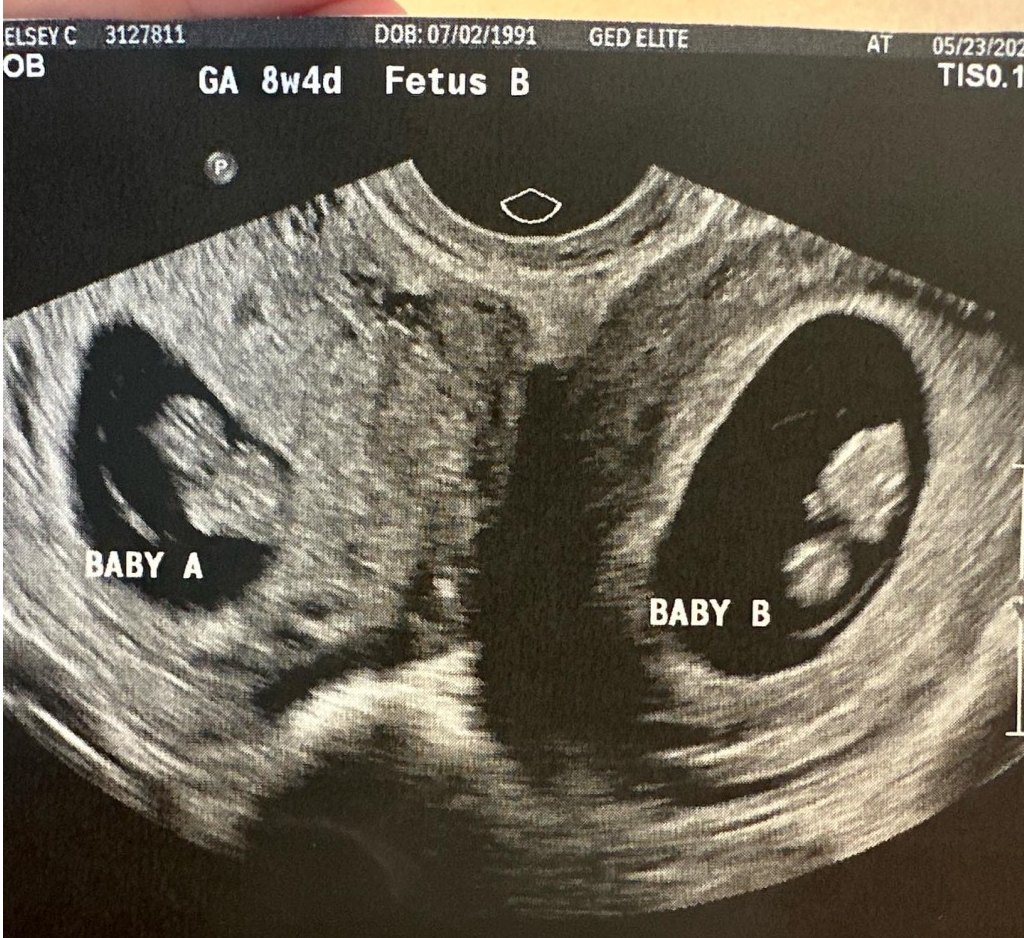

B超檢查顯示,凱爾西·哈徹的兩個子宮同時妊娠。圖源/IG

今年5月,凱爾西懷孕八週,做了第一次產檢。B超醫生看到胎兒一切正常、很健康。凱爾西提醒醫生再照照另一邊,因為她有着異於常人的生理結構。

B超醫生把超聲波頭移到腹部另一側。不一會兒,醫生驚呼:“天哪,這裏還有一個。”